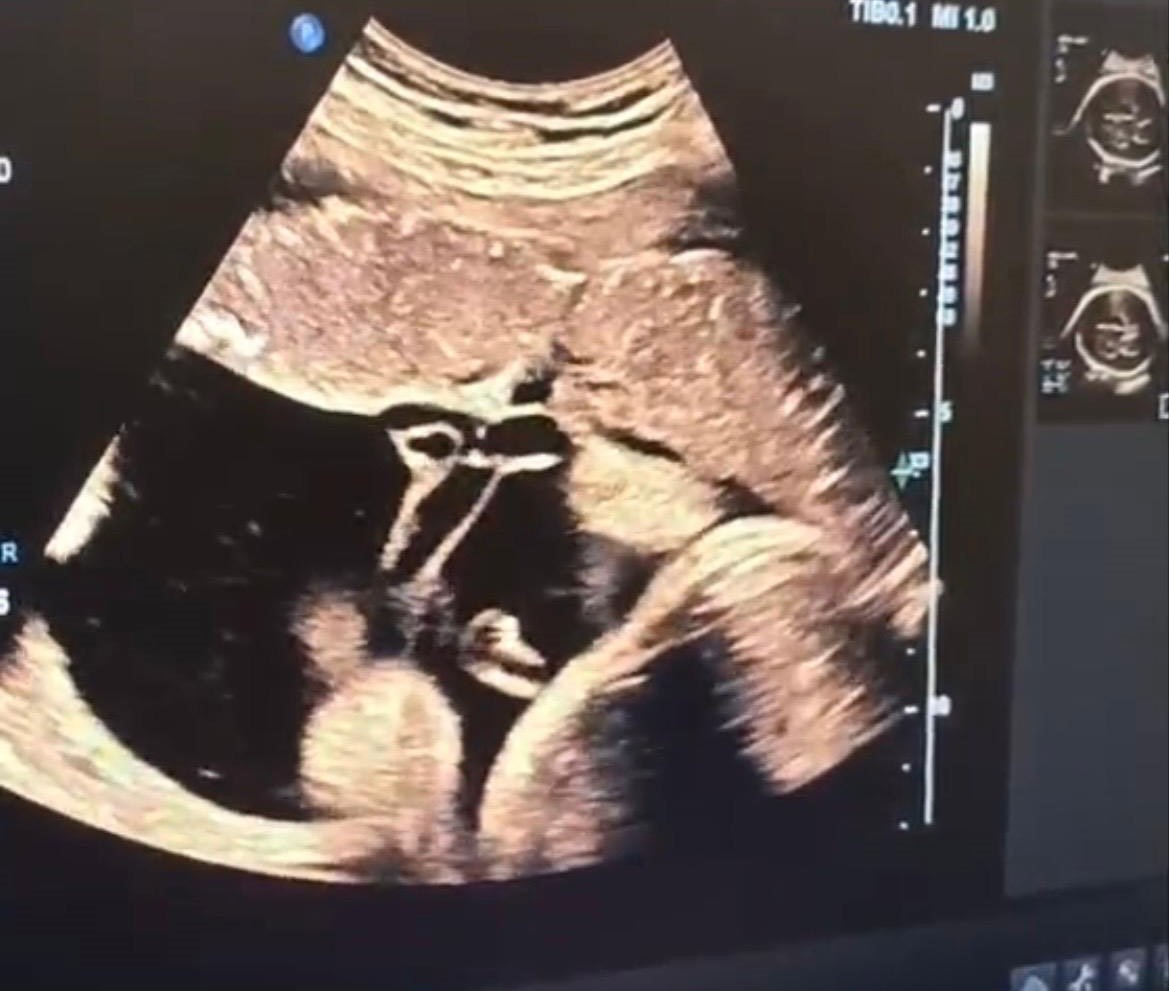

Halk arasında “anne karnında kan nakli” olarak bilinen intrauterin fetal kan transfüzyonu, bebekte ciddi kansızlık (anemi) tespit edilmesi halinde uygulanan hayati bir tedavi yöntemi olarak biliniyor. İşlem, ultrason eşliğinde anne karnından ince bir iğne yardımıyla bebeğin göbek kordonuna girilerek gerçekleştiriliyor. Önce bebeğin kan değerleri ölçülüyor, ardından eksik olan miktar kontrollü şekilde naklediliyor. Lokal anestezi altında ve steril şartlarda yapılan müdahale yaklaşık 30-45 dakika sürüyor.